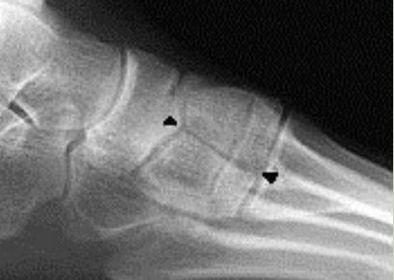

| What is this? What is shown by A and B? | STJ coalition A = talar neck spurring B = Halo or 'C' sign |

| What is this? | Posterior talocalcaneal coalition |